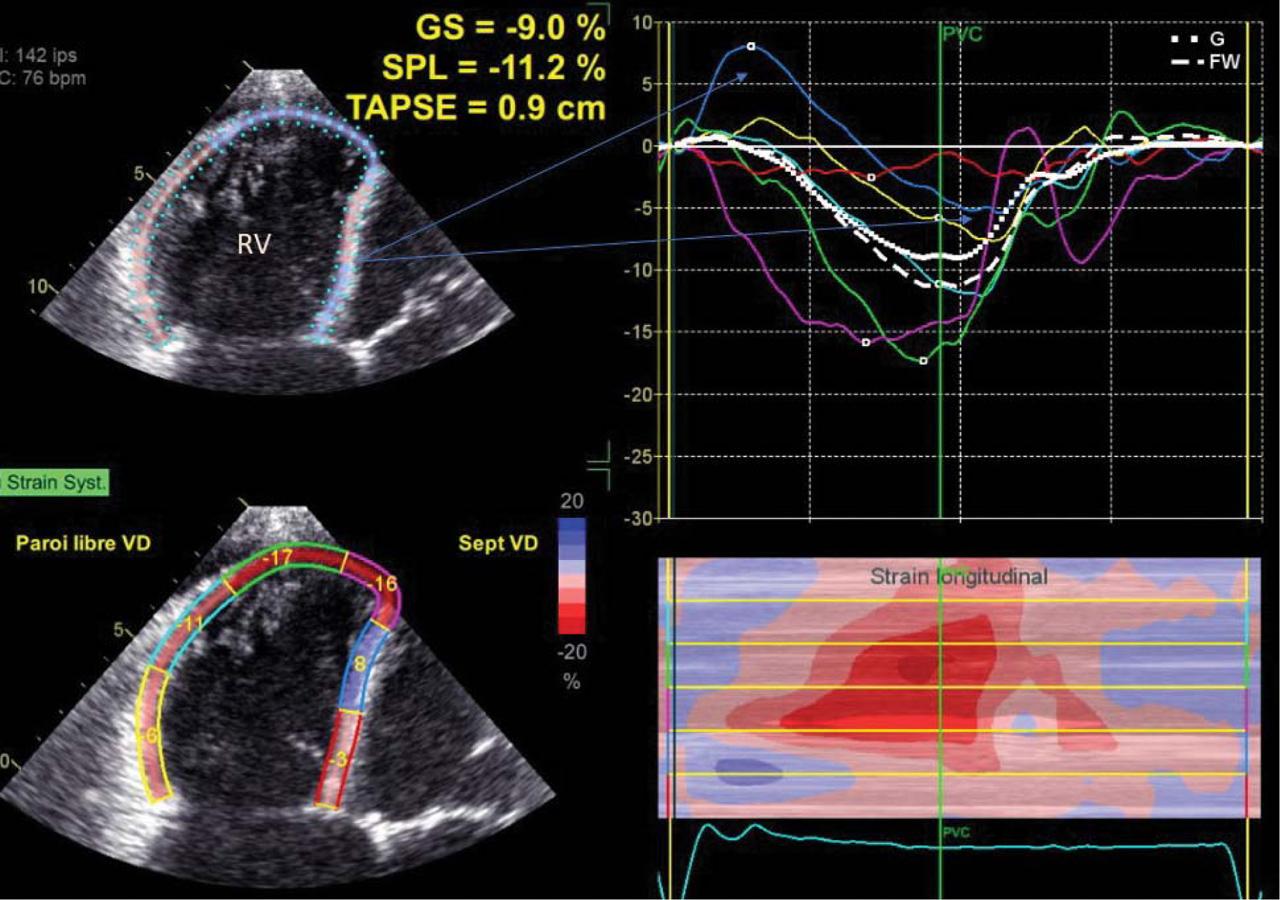

Figure 5

A) As a consequence of the right ventricle dilatation and dysfunction, the interaction with the left ventricle lead to a left ventricular dysfunction. B) Delayed deformation of the septum, even elongation in early systole: consequence of the volume overload of the right ventricle in a patient with a severe tricuspid regurgitation.